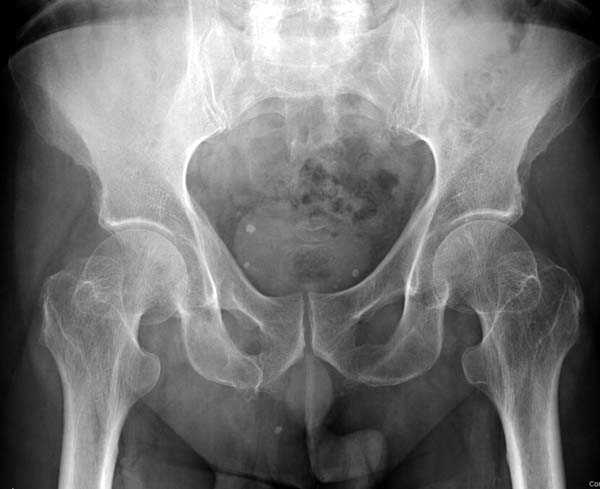

Почему неполный перелом? Я бы назвал его вколоченным!

Перелом конечно не вколоченный т.к. видно линию перелома и нет суперпозиции костной ткани.

Добрый день. Перелом коварный. Через время может произойти лизис в области "неполного" перелома и он превратиться в "полный" со всеми очевидными проблемами, тем более у пациента, склонного к питию. Если не разовьется делирий или после выхода из него, рекомендую внутренний остеосинтез винтами.

Профилактику дальнейшего раскола неполного перелома шейки провели тремя канюлированными шурупами.